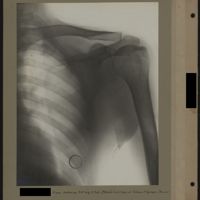

0032 - Page 28 - [Radiographie de l'épaule]0032 - Page 28 - [Radiographie de l'épaule]